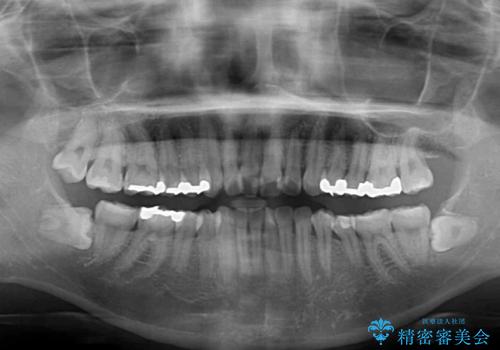

- 上の前歯の捻じれと突出感を気にして来院された患者様です。

目立たない装置を希望とのことで、上顎左右第一小臼歯を抜歯し、インビザラインにて矯正治療を行うこととしました。